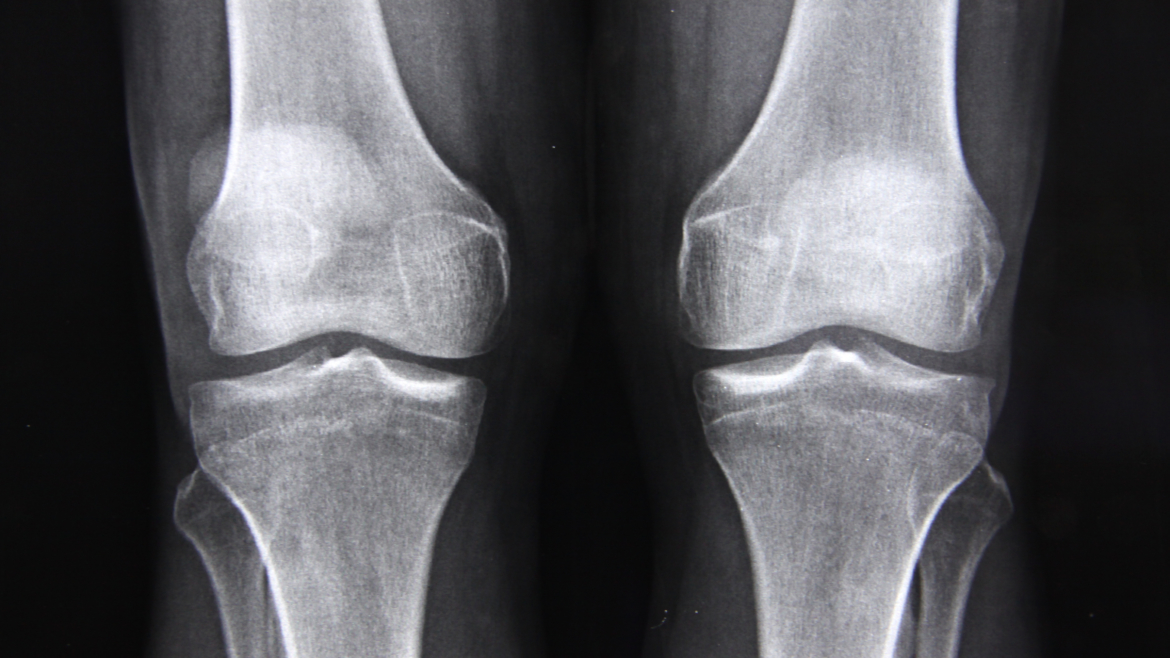

Osteoporos, även kallat benskörhet, och där till kopplade osteoporosfrakturer, är en av de vanligaste svenska folksjukdomarna och som drabbar varannan kvinna över 50 år. Vid osteoporos blir skelettet skört och kan lätt brytas, det kan i de svåraste fallen räcka med en hostning. Det finns verkningsfull behandling men långt ifrån alla kvinnor får ta del av denna behandling.

Med över 200 ben i vår kropp är kunskap om vad benskörhet (Osteoporos) är och hur det behandlas, och hur du själv kan förebygga sjukdomen, viktig.

Benskörhet är en vanlig åkomma hos kvinnor efter klimakteriet. Många drabbas av skelettskador med smärta, funktionshinder och nedsatt livskvalitet som följd. Värst är frakturer på ryggkotor som ger ett mycket långvarigt lidande, visar en doktorsavhandling vid Linköpings universitet.